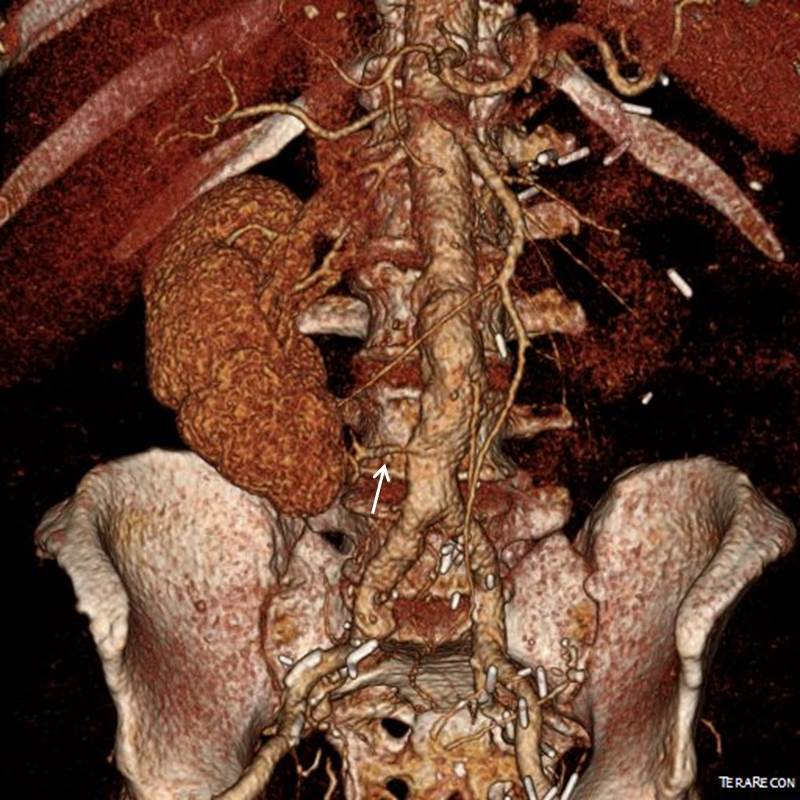

A Troublesome Accessory Renal Artery Complicating a Complicated Patient

Preop Figure

The patient is an 65 year old man with a growing right common iliac artery aneurysm of 3.7cm, a small AAA, and severe COPD (not oxygen dependent, FEV 1.5L) . He had a prior left nephrectomy for cancer as well as a bladder resection and prostatectomy with an ileal conduit (Indiana pouch or neobladder), with complex abdominal wall closure complicated by infection of Marlex in the past, and prior operations for small bowel obstruction. He is morbidly obese. His kidney function was stable with a Cr 1.5dL/mL, calculated GFR or 44mL/min. His nuclear cardiac stress test (pharmacologic) was normal.

A magnified view of the accessory renal artery is shows below with the arrow

mag preop CT

He needed to have his right CIAA treated but the issues were what to do with his accessory renal artery. Vascular surgery is all about making the right decisions with fall back plans. As with most complicated patients, the options are numerous.

I informally polled my partners and found an absence of consensus except for rejecting #1, 2, and 7. The first two options were not optimal because of his prior operation and because of the location of his disease. The third option had its proponents, but I felt that the kidney and pouch were in jeopardy from dissection in that area. The open debranching had its appeal for others, but for the same reasons that I rejected #3, I rejected #4 –potential harm to the kidney. #5 may be an option, but in my experience, I have seen too many patients referred for failure of parallel grafts to feel secure about offering it.  #6 would be reasonable if the patient could avoid dialysis. With a calculated CGF of 44ml/min, losing half the remaining kidney would barely leave him off dialysis. By appearances though, the smart money was on losing less than 50% but more than 20%. A 30% loss would result in a GFR of 30mL/min or a Cr of 2.1 which made dialysis not likely. In my experience, the kidney does have some collateralization as evidenced by backbleeding of accessory renals with an infrarenal clamp so it may be that he might lose only 10-15%. I discussed all of these options and medical management with the patient who agreed to proceed with option 5 under my recommendation. My plan was to assess the flow from the accessory renal and proceed if it was small, with plan B being a parallel graft, plan C debranching.

nephrogram

In the OR, the right accessory renal artery was selectively catheterized and a nephrogram revealed that it supplied less than 20% of the kidney. The above diagram shows the extent of the total kidney and the area perfused by the accessory renal artery. I proceeded with coil embolization of it and the right hypogastric artery and EVAR of the AAA/R.CIAA.

post CT

In followup, the patient had a Cr of 1.7mg/dL, representing about 15% loss of kidney function. As the case was done percutaneously, he only had 1cm incision in both groins, and was pleased with his result. No endoleak was seen (CT above).

The telling lesson about this case is that at the time of initial consultation, my first instinct was to prepare the patient for open repair via a right retroperitoneal approach with debranching of the right accessory renal artery as a fallback position. Open surgery is my fallback as it was the foundation of my training. But experience has also taught me that patients with multiple comorbidities often struggle to recover from big operations even if one particular problem is not prohibitively severe. Finally, having smart partners to bounce ideas off of is a not only a luxury but a critical asset.